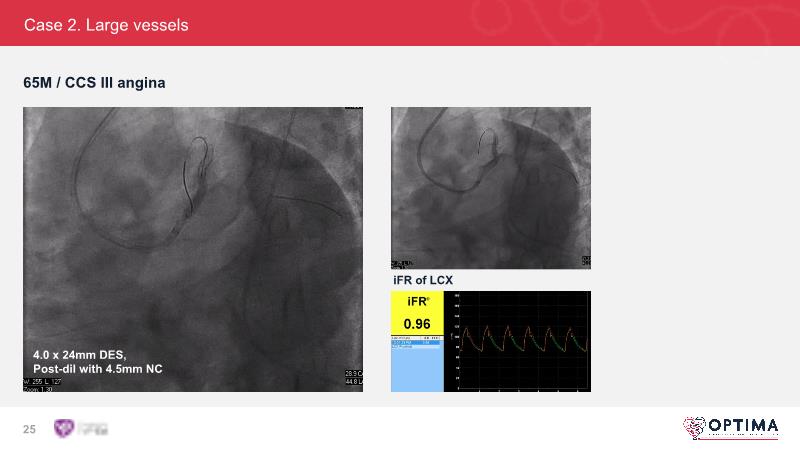

Cracking calcium: intravascular lithotripsy’s unique mode of action in treating calcified lesions – What's the evidence?

Watch this GulfPCR-GIM 2022 session to understand the unique mechanism of action of IVL, the use of intravascular imaging in calcium identification, the gender gap, disrupted CAD trials, and the evolution of treatment of calcified lesions together with the role of IVL.

- To understand the evolution of treating calcified lesions and the role of intravascular lithotripsy